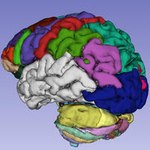

Multi-modality MRI-based Atlas of the Brain Slicer4.5 08/2015 version |